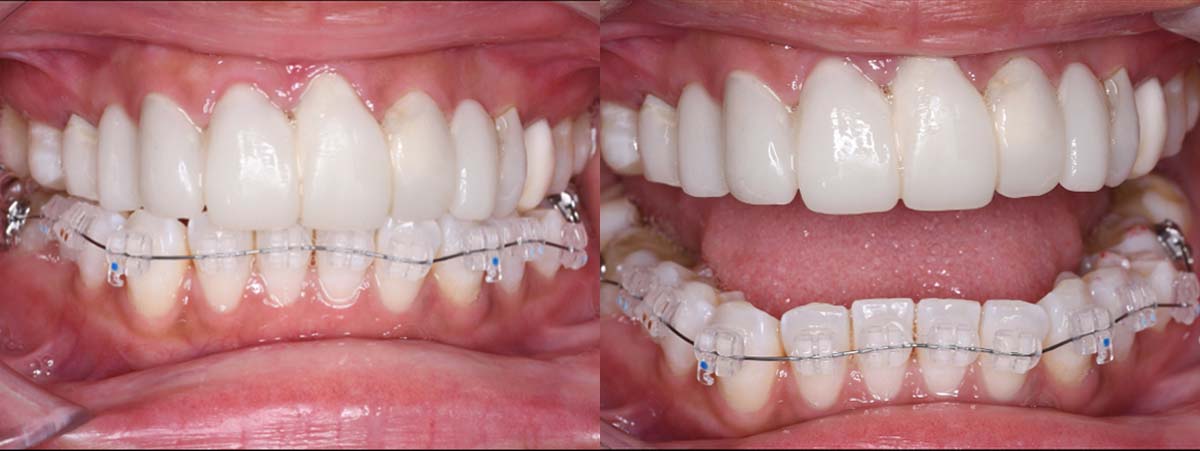

スプリント使用後、

補綴治療をした症例

副子なし 副子あり

バイトアップ後